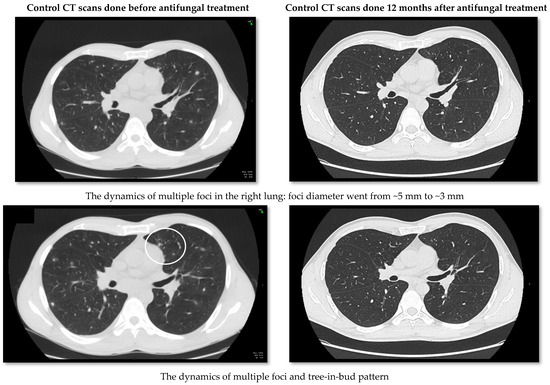

2. Case Report